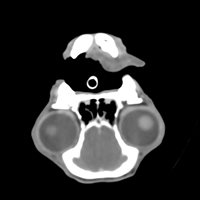

The scanner gives the possibility to diagnose certain pathologies earlier and more precisely than with other imaging techniques (ultrasound or radiography). Like humans, the scanner allows veterinarians to view and examine parts of the body that are usually difficult to assess with conventional x-ray images.

The areas most commonly explored by CT scans in animals are the skull, spine, thorax, abdomen and certain joints such as the elbow or shoulder.

Nasal Cavities

- Suspicion of Aspergillosis, tumour or foreign body in the nasal cavities